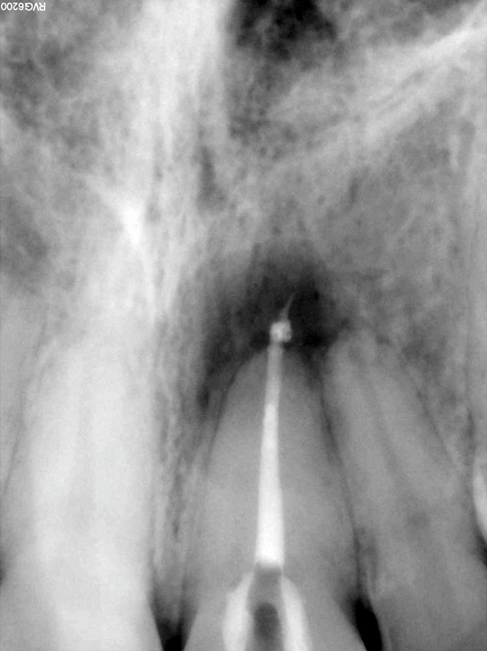

(5.) Preoperative radiograph of tooth No. 19 following a pulpectomy procedure that was complicated by an intraoperative furcal perforation.

Figure 5

(6.) Postoperative radiograph showing immediate perforation repair using MTA followed by complete obturation.

Figure 6